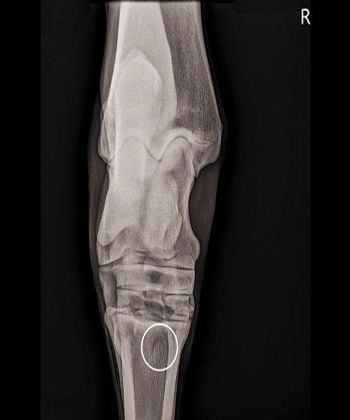

Rigorous evaluation techniques and diagnostics are key for veterinarians to identify lameness early and for successful treatment.